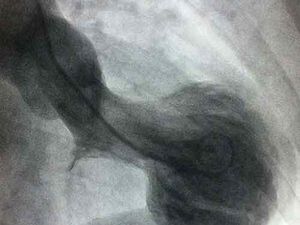

Patah hati bisa berbahaya! Kenali Broken Heart Syndrome yang mirip serangan jantung. Pria berisiko lebih tinggi. Segera periksa jika mengalami gejala.